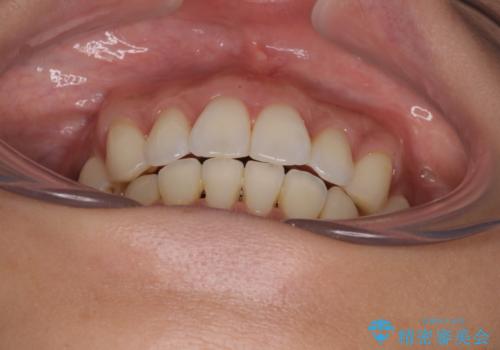

出っ歯になることなく、上下前歯が綺麗に接触する状態で仕上げることができました。